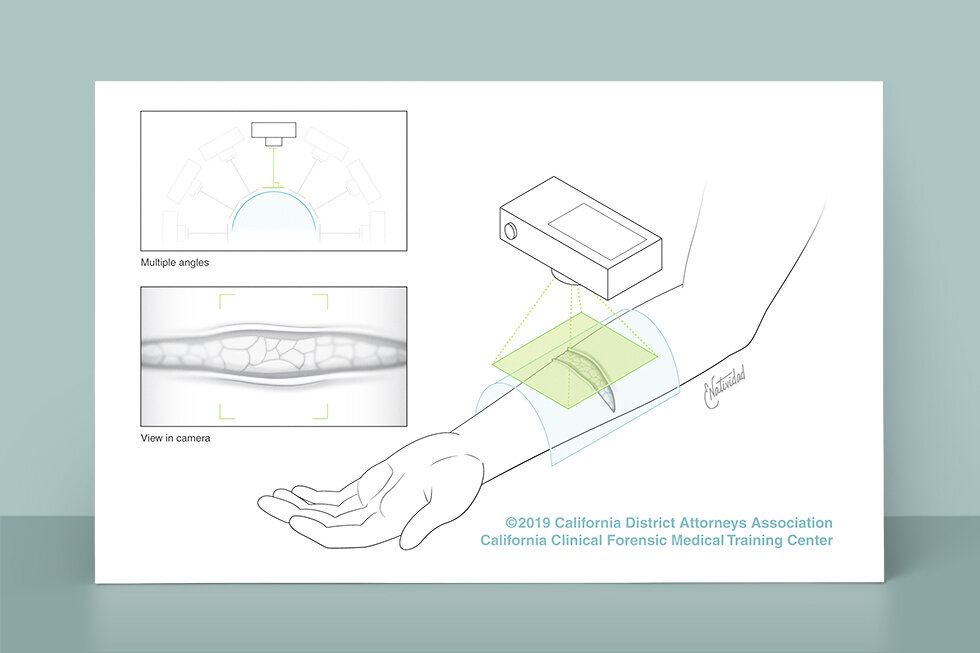

Running series of animated visual abstracts, Quick Takes, created for The New England Journal of Medicine as part of a team of illustrators, medical writers, and scientists. These short, iconographic animations aim to succinctly describe clinical trials and increase the awareness and understanding of important research findings.

Adopting The Journal’s visual style and asset library, I am responsible for the entire production process including narration editing, storyboarding, layout, illustration, and animation.